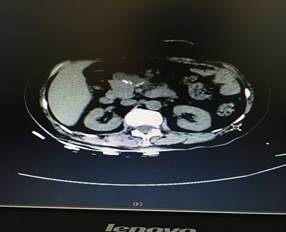

充分術(shù)前準(zhǔn)備后,在肝膽外科團(tuán)隊(duì)努力及麻醉科的鼎力支持下,歷經(jīng)4個多小時(shí),大家成功在腹腔鏡下為患者進(jìn)行了胰腺巨大腫瘤及胰腺體尾端切除,脾臟、膽囊切除手術(shù)。術(shù)后第四天患者便進(jìn)食流汁,下床活動,復(fù)查情況良好(圖2、圖3),患者和家屬臉上都露出了久違的笑容。

圖2

圖3